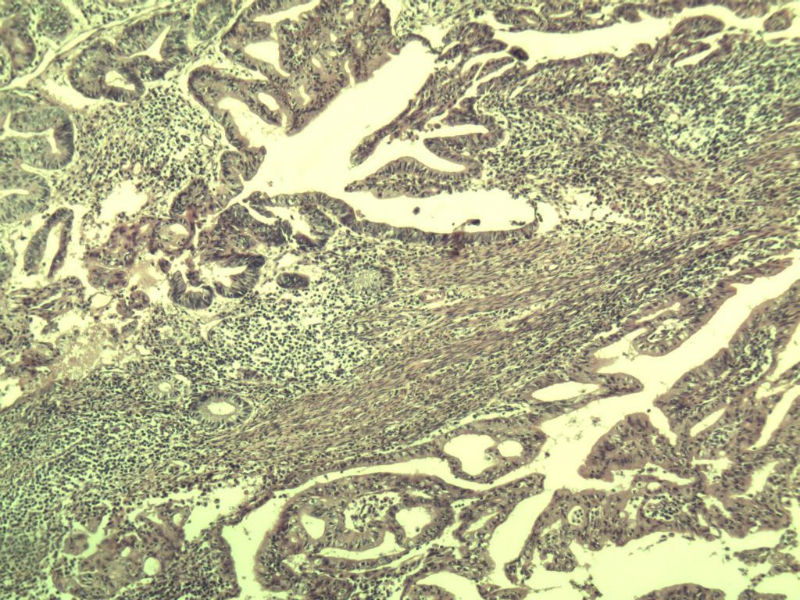

女,57岁,全切子宫一个,宫体体积 9 × 8 × 7 cm3,肌壁厚 2.5 cm,内膜菲薄,部分区域增厚达 0.4 cm(约3*2.5cm区域)。 请问各位老师  这个可以诊断子宫内膜癌了吧?      深肌层没有看到浸润。

患者因"发现下腹部包块1月多"入院  宫体体积 9 × 8 × 7 cm3,肌壁厚 2.5 cm,内膜菲薄,部分区域厚 0.4 cm(约3*2.5cm)。宫颈结构不清,长约 2.5 cm,表面欠光滑。临床诊断宫颈宫腔积液.

宫内膜样腺癌

筛状、迷路样结构

间质消失或者纤维性间质

子宫内膜样腺癌

高分化子宫内膜样癌。浸润浅肌层(深度<1/3肌层)。根据FIGO2009分期,子宫内膜癌局限于内膜层和<1/2肌层,都属于IA期。二者处理不再区别对待。